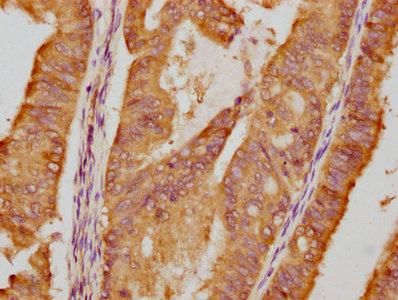

IHC image of CSB-RA011087A1HU diluted at 1:87.5 and staining in paraffin-embedded human endometrial cancer performed on a Leica BondTM system. After dewaxing and hydration, antigen retrieval was mediated by high pressure in a citrate buffer (pH 6.0). Section was blocked with 10% normal goat serum 30min at RT. Then primary antibody (1% BSA) was incubated at 4℃ overnight. The primary is detected by a biotinylated secondary antibody and visualized using an HRP conjugated SP system.